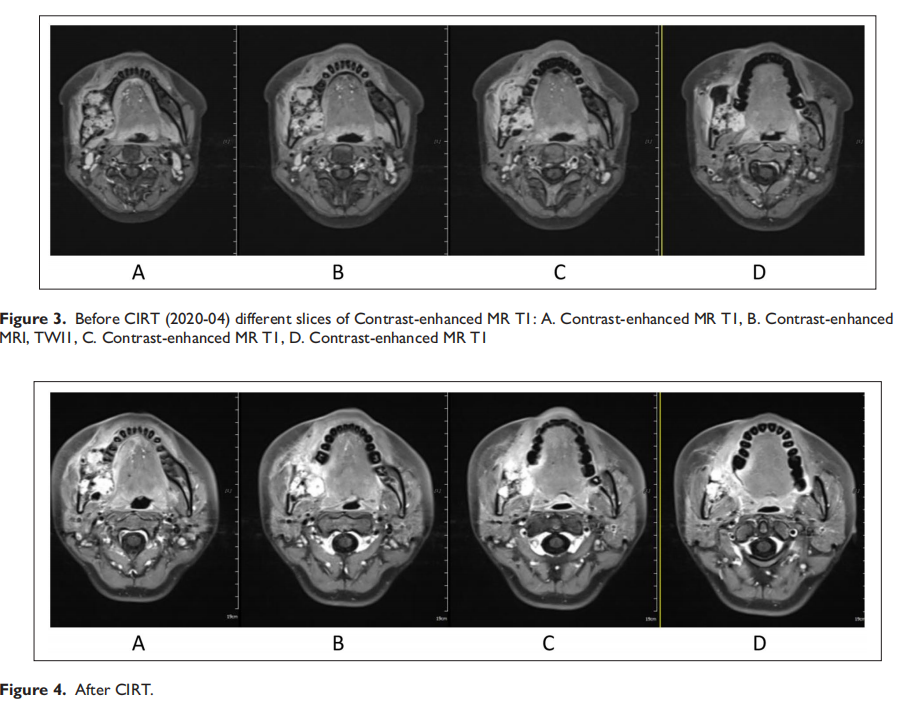

Carbon ion radiotherapy for recurrent ameloblastoma: A case report